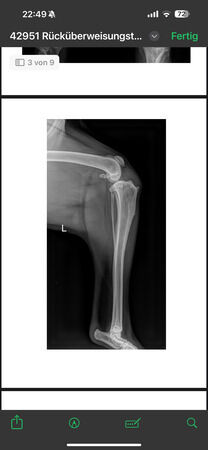

steht vorne sehr breit/ O-beinig, hi. re. Mitte Unterschenkel amputiert,

Knie li. deutlich verdickt, aber keine deutliche Instabilität.Verdickung hauptsächlich am

Oateöllasehnenansatz

radiologisch kein Kniegelenkserguß oder Arthrose, nur Weichteilschwellung im Bereich distaler

Patellasehne, Elle proximal verdickt und Fehlstellung (alte, verheilte Fraktur?), keine deutlich

Ellbogenarthrose, leichtgradige Fehlstellung Unterarm li., auch leichtgradige Fehlstellung Radius re.

Alle Gelenke sonst ohne deutliche Arthrosezeichen.